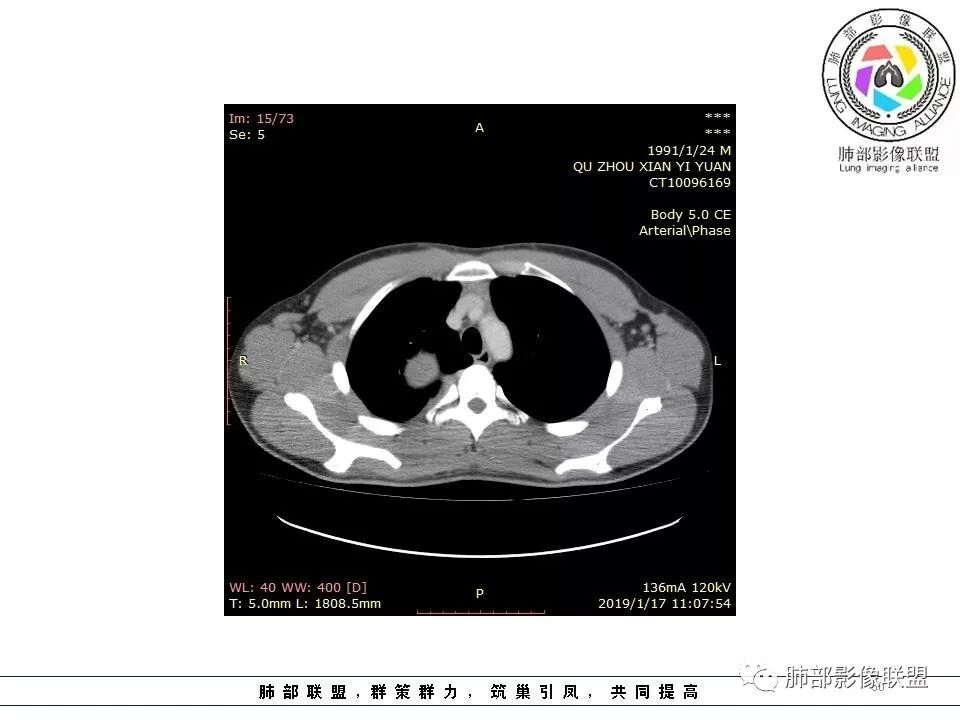

青年男性,间断胸痛;右侧脊柱旁可见一类圆形软组织密度影,密度欠均匀,增强扫描呈轻中度持续强化,邻近肺组织及肺动脉推移,可见肋间动脉供血,部分胸膜下脂肪可见,部分层面似见与右侧椎间孔相连。考虑后纵隔神经源性肿瘤。

青年男性,右侧脊柱旁软组织肿块,边缘膨隆,密度不均,临近肺组织受压、胸膜增厚,增强后动脉期呈不均匀强化,并可见肋间动脉供血,延迟期强化较均匀,定位肺外,首先考虑SFT,神经源性肿瘤待排

右肺占位,跨越上叶后段、下叶背,边缘光滑,瘤肺界面清,见肺压缩缘(线样不张`强化),见胸膜尾征,胸膜下脂肪未见明显增厚,肋骨丶脊柱未见侵袭及受压,渐进性丶地图样强化,冠状位似见体循环供血

诊断:SFT(来源壁层胸膜?一般小于20%)

鉴别:神经源性(鞘瘤)、LCD、肉瘤丶孤立性间皮瘤

青年男性,右后上纵隔脊柱旁沟可见团状软组织影,边界清,密度尚均匀,推挤邻近肺组织,胸膜可见掀起,有肺动脉供血,增强轻度蛇皮样强化,纵隔淋巴结未见肿大,邻近骨质未见破坏,胸膜下脂肪间隙消失,考虑SFT孤立性纤维瘤可能性大,鉴别神经鞘瘤,节细胞瘤,建议活检。

青年男性,胸痛,右上纵膈脊柱旁肿块,形态光整规则,支气管被推移,临近的胸膜明显增厚,有胸膜掀起,增强后密度不均匀,可见蛇形血管征,血供似乎有两根血管供血,考虑SFT

右后纵膈肿块,肺瘤界面清楚,胸膜尾征,邻近肺组织及支气管被推移,部分脂肪间隙存在,定位肺外来源,血供来自肋间动脉,增强后持续渐进强化,蛇纹征,考虑SFT,鞘瘤肿块内血管罕见,不考虑。

右上肺野脊柱旁软组织肿块,边缘光滑整齐,肺组织及气管右肺上叶支气管受压前移,外移,边缘可见胸膜尾征,病灶内密度不均,增强后渐进性持续强化,其内可见明显蛇纹血管征,首先考虑肺外来源,sft.可能性大

青年男性,右侧脊柱旁占位,瘤肺界限清晰,支气管推移,胸膜尾,D字征,胸膜下脂肪影,蛇纹血管,双重供血,延迟强化,定位胸膜,支持sft

1.右上胸内脊柱旁类圆形肿块,质地似乎比较坚实,密度稍显不均,但未显示明确的坏死。

如此密度形态的病灶位于肺边缘首先应当想到孤立性纤维瘤,可相邻胸膜未见明显的异常强化和胸膜方向延伸。

2.肋间动脉病供血也提示肿块来自后纵隔?

4.静脉期轻度不均匀强化,注意不是环形强化,亦未见明确的“AB区”,这点也不支持神经鞘瘤。临床及病灶轻度强化都不支持副节瘤。